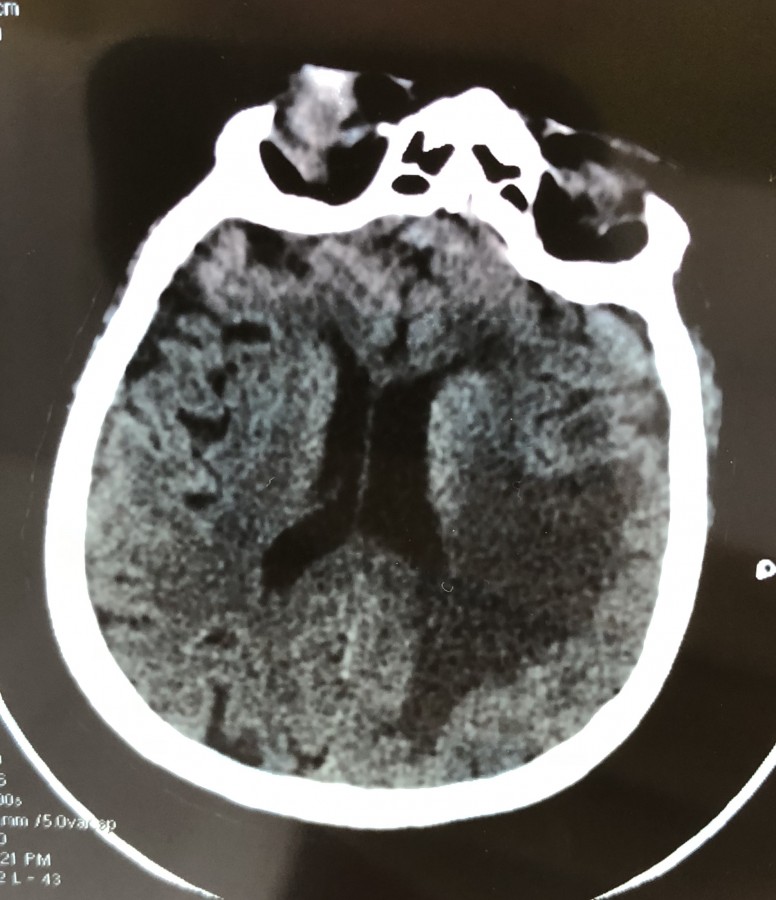

„Pacienta a fost diagnosticată în cadrul serviciului nostru cu o tumoră cerebrală gigantă localizată pe linia mediană a craniului, adică în mijlocul creierului. Particularitatea cazului a constat în faptul că, pe lângă această tumoră situată foarte profund, pacienta a prezentat, în apropiere, și o hemoragie cerebrală. După pregătirea atentă a cazului, am intervenit practicându-se rezecția completă a tumorii și evacuarea completă a hematomului, simultan”, explică Șef Lucrări Dr. Vicențiu Săceleanu.

Intervenția chirurgicală, efectuată cu microscopul operator performant din dotarea secției, a durat opt ore iar dimensiunea tumorii a fost de 6/4 cm. Operația a fost un succes, controlul post operator indicând evacuarea completă a celor două leziuni.

„Gradul ridicat de dificultate a intervenției a fost dat de asocierea acestei tumori profunde cu interesarea liniei mediene, cum o numim în neurochirurgie, adică sinusul sagital superior, practic cea mai mare venă din craniu, existând astfel riscul unei hemoragii masive în timpul operației. Ne exprimăm satisfacția că această operație a fost o reușită, fapt care denotă profesionalismul colectivului secției de neurochirurgie a Spitalului Clinic Județean de Urgență Sibiu și buna colaborare cu Universitatea Lucian Blaga, Facultatea de Medicină”, precizează Șef Lucrări Dr. Vicențiu Săceleanu.În momentul de față pacienta se află sub supraveghere post-operatorie de specialitate, este stabilă, cu evaluare neurologică bună și va intra într-un program de recuperare.